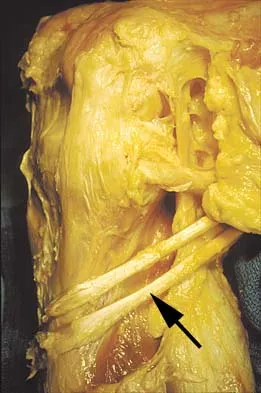

Question 45

Figure 11 shows the anatomic dissection of the medial side of the knee joint after removal of the superficial fascia. The arrow is pointing to what structure?

Explanation